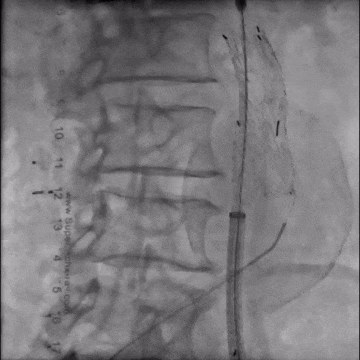

手术采用腹主分支支架,主体释放后行交叉腿髂支延伸。

造影示肾下腹主动脉瘤

选用28-14-140mm主动脉覆膜支架

释放短腿(交叉腿)

导丝超选右髂支

右侧延续16-18-140mm髂支

左侧延续16-18-140mm髂支

术中释放右侧髂支后,患者突发腹痛、心率增快、血压下降,造影怀疑右髂动脉破裂,紧急加放髂支并弹簧圈栓塞。